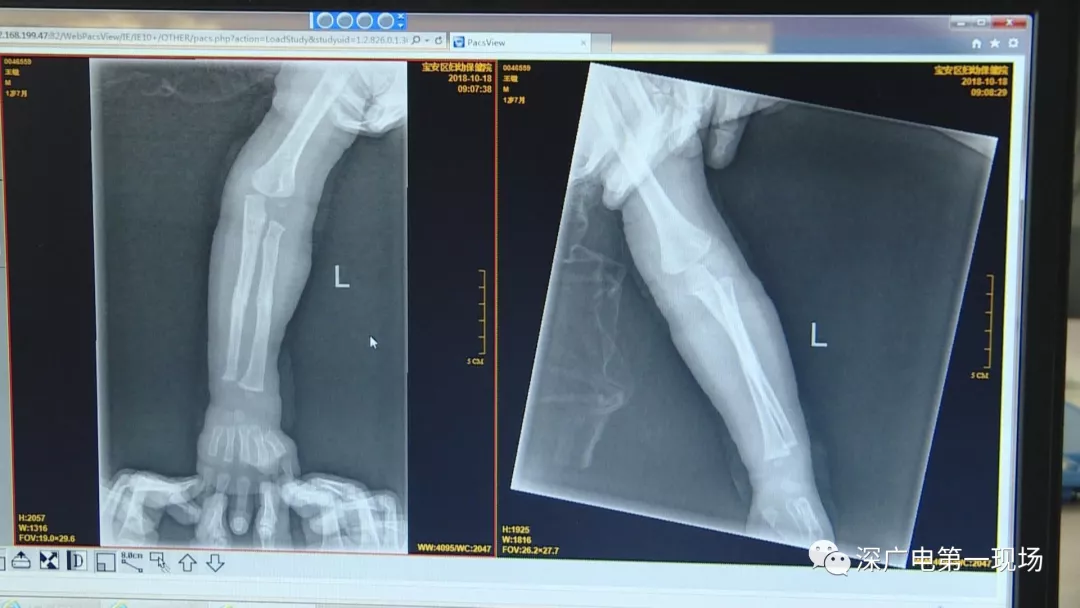

一名1歲多的男嬰摔斷了胳膊

9月4號(hào),一名1歲零5個(gè)月的男嬰因在家中摔傷,被父母送到了寶安區(qū)婦幼保健院,醫(yī)生診斷為左側(cè)尺橈骨骨折。在進(jìn)行全麻手術(shù)之前,院方例行對(duì)嬰兒進(jìn)行了周身檢查。手術(shù)前,兒外科醫(yī)生趙冠聰在查看患者的胸片時(shí),發(fā)現(xiàn)這名嬰兒的胃部有一枚硬幣大小的暗影。